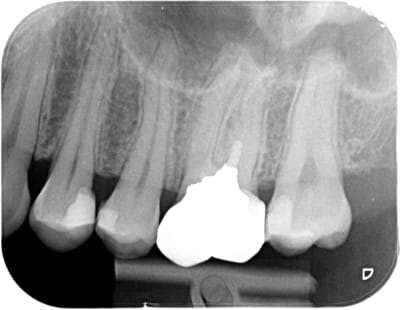

Spécial dédicace au "blanc" en mésial de la 7 derrière une cc... logique implacable ;)